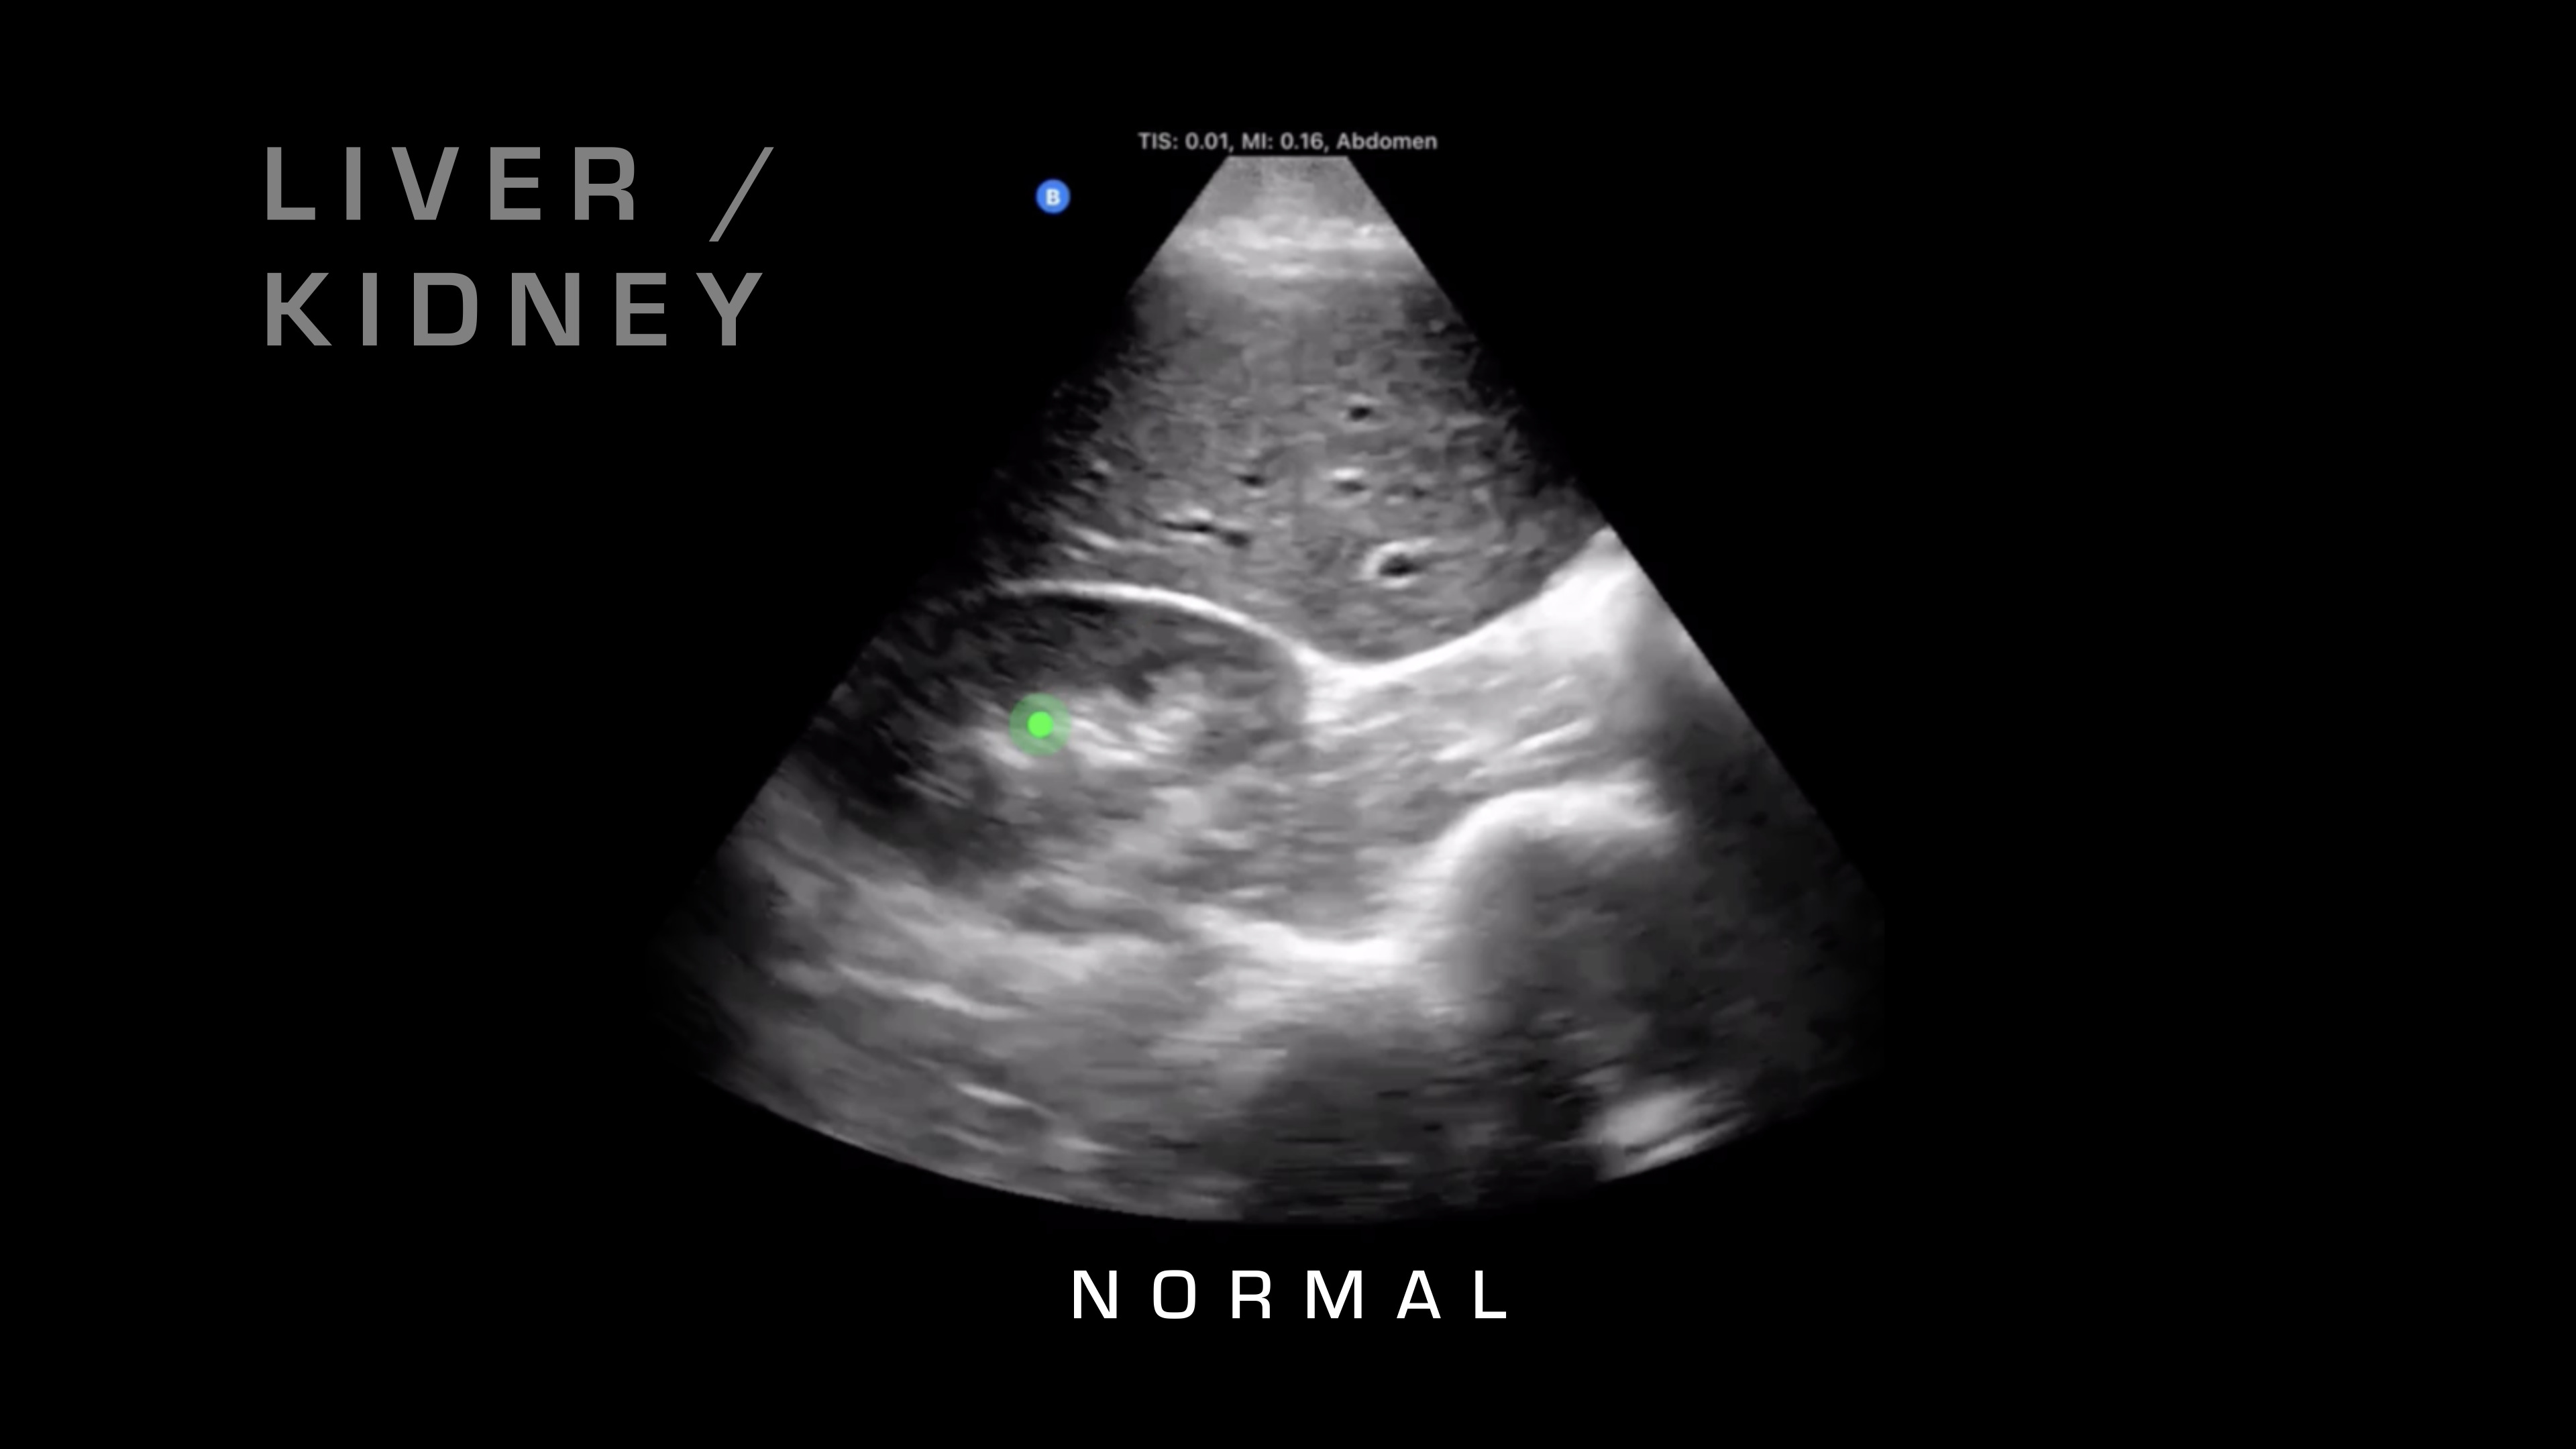

Liver & Kidney

If I want to go superficial, I'll swipe it down. If I want to go deeper, I'm going to swipe up and take a look. Next up, I'm going to go over on the right side of the patient, and what I'm going to be looking for is the liver and where that interfaces with the kidney. So there's a potential space there that shouldn't have any fluid between it, and if you see fluid between it, as you can see on this video here, then that's blood in the abdomen. So you know your patient is bleeding internally. That's obviously a risk for hemorrhagic shock, and that would warrant resuscitative care and rapid evacuation.